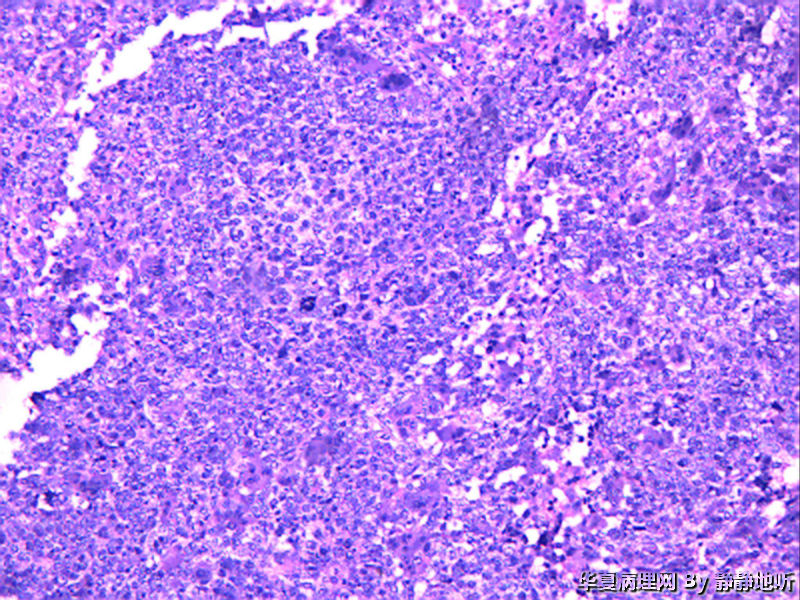

• 子宫肿瘤图2

图2

女性46岁,子宫峡部肿瘤,息肉样,体积3.5*4*3厘米,脱入宫颈,大体侵肌层。子宫肌壁明显增厚,大体似子宫腺肌症。

免疫组化:ck7-    CEA-    ER -   PR -   CD10 -   Vimentin -   ki-67 约60%